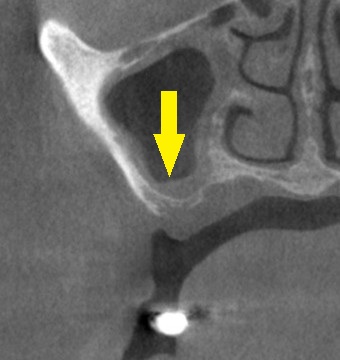

CTを撮影してみると、第二小臼歯部は骨幅が狭く(下の写真上段左)、第一大臼歯部は骨が薄く、高さが不足していました(下の写真上段右)。

第一大臼歯には人工骨は使用せず、患者様ご自身の骨を上方に持ち上げ、ワイド径のインプラントを埋入する計画としました。